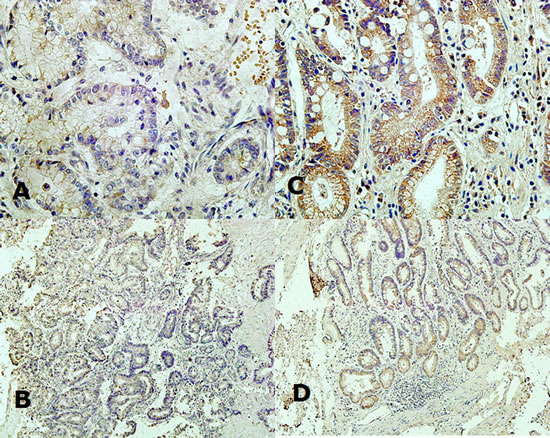

RNF180 protein expression was mainly observed in the cytoplasm (Figure 1). RNF180 protein expression was detected in 38 (56.72%) (-), 13 (19.40%) (+), 10 (14.92%) (++), and 6 (8.96%) (+++) tumor samples, which represented that only 16 (23.88%) patients presented positive RNF180 protein expression. Meanwhile, we found that 7 (10.45%) (-), 21 (31.34%) (+), 19 (28.36%) (++), and 20 (29.85%) (+++) of RNF180 protein expression were detected in paired adjacent non-tumor tissues, respectively. Therefore, we demonstrated that the positive rate of RNF180 protein expression in gastric cancer tissues was significantly lower than that in adjacent non-tumor tissues (P <0.001).

Fig. 1: (A) Expression of RNF180 protein in the cytoplasm of malignant epithelium of gastric cancer tissue (x400 magnification); (B) Expression of RNF180 protein in the cytoplasm of malignant epithelium of gastric cancer tissue (x100 magnification); (C) Expression of RNF180 in the cytoplasm of epithelium of paired adjacent non-tumor tissue (x400 magnification); (D) Expression of RNF180 in the cytoplasm of epithelium of paired adjacent non-tumor tissue (x100 magnification).